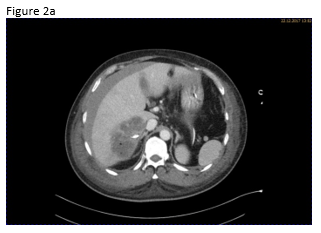

A 49 year old patient was admitted to the hospital for sepsis and shock of unknown origin. The patient presented with signs of sepsis and hemodynamic instability that justified an urgent approach including complex intensive care and intubation. Bedside ultrasound (US) found ascites and an abscess in the right liver lobe (9 cm) (Figure 1a). The patient was treated with broad-spectrum antibiotics and puncture and drainage of the abscess (Figures 1 a-c and 2 a-b). In addition, a biopsy was taken from the periphery of the lesion. A few days after the removal of the drainage the patient presented with a progressive elevation of liver enzymes. US revealed a cystic lesion measuring 30 mm that was proximal to the drained abscess (Figure 1a). Color Doppler Imaging (CDI) showed arterial flow inside the lesion, and contrast enhanced ultrasound (CEUS) showed early arterial enhancement and turbulent flow with a “to-and-fro” sign, suggestive of a pseudoaneurysm (Figure 1b). There was also a heterogeneously vascularized lesion with enhancing septae in the surrounding liver parenchyma (Figure 1c) . A few days later the patient presented with tachycardia and a drop of hemoglobin from 10 g/dl to 7 g/dl. US revealed spontaneous thrombosis of the pseudoaneurysm (Figure 1d) with intra - and perihepatic hemorrhage (Figure 1e).

Figure 2: Computed tomography (CT)showed abscess formation before drainage and perihepatic ascites (a). Twelve days after drainage removal a CT follow-up showed hyperenhancing intrahepatic lesion in proximity of the abscess, suggestive of a pseudoaneurysm (b). CT confirmed the spontaneous thrombosis of the pseudoaneurysm (c).